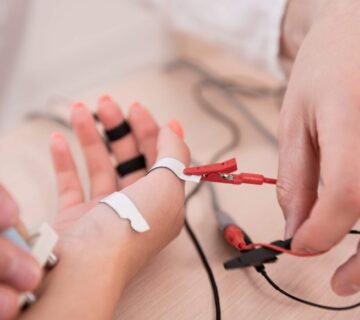

- مطالعات هدایت عصبی (NCS): در این مرحله، هدایت عصبی در اعصاب محیطی اندازهگیری میشود. این آزمون شامل ارسال سیگنالهای الکتریکی کوچک به اعصاب و اندازهگیری پاسخ آنها است. کاهش سرعت یا شدت پاسخ میتواند نشاندهنده آسیب عصبی باشد.

- الکترومایوگرافی (EMG): در این آزمایش، الکترودهای سوزنی نازک به عضلات مختلف وارد میشوند تا فعالیت الکتریکی عضلات در حالت استراحت و انقباض بررسی شود. EMG میتواند نشان دهد که آیا ضعف عضلانی به دلیل آسیب به اعصاب است یا ناشی از مشکلات عضلانی.

استفاده از EMG و NCS به تشخیص دقیقتر نوروپاتی دیابتی کمک میکند. این آزمایشها میتوانند به پزشکان نشان دهند که کدام اعصاب تحت تأثیر قرار گرفتهاند و میزان آسیب چقدر است. این اطلاعات برای تنظیم برنامه درمانی مناسب بسیار حیاتی است و میتواند به پیشگیری از پیشرفت بیماری کمک کند.